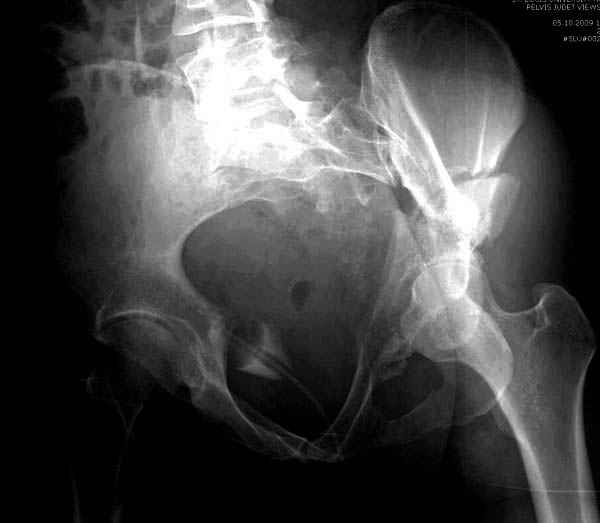

Все выступающие коллеги высказались насчет необходимости стандартных снимков по Judet, потому что для определения тактики лечения переломов вертлужной впадины 3Д снимки малоинформативны.

Летурнель разработал классификсацию на основании прямого, запирательного и подвздошного рентген снимков, котоые, кроме описания характера переломов, также подсказывают адекватный доступ для репозиции перелома.

Из того минимума, что представлено, мне кажется, мы имеем дело с двухколонным переломом вертлужной впадины. Обычно медиальный (центральный) "вывих" головки встречаются в сложных двухколонных переломах со смещением.